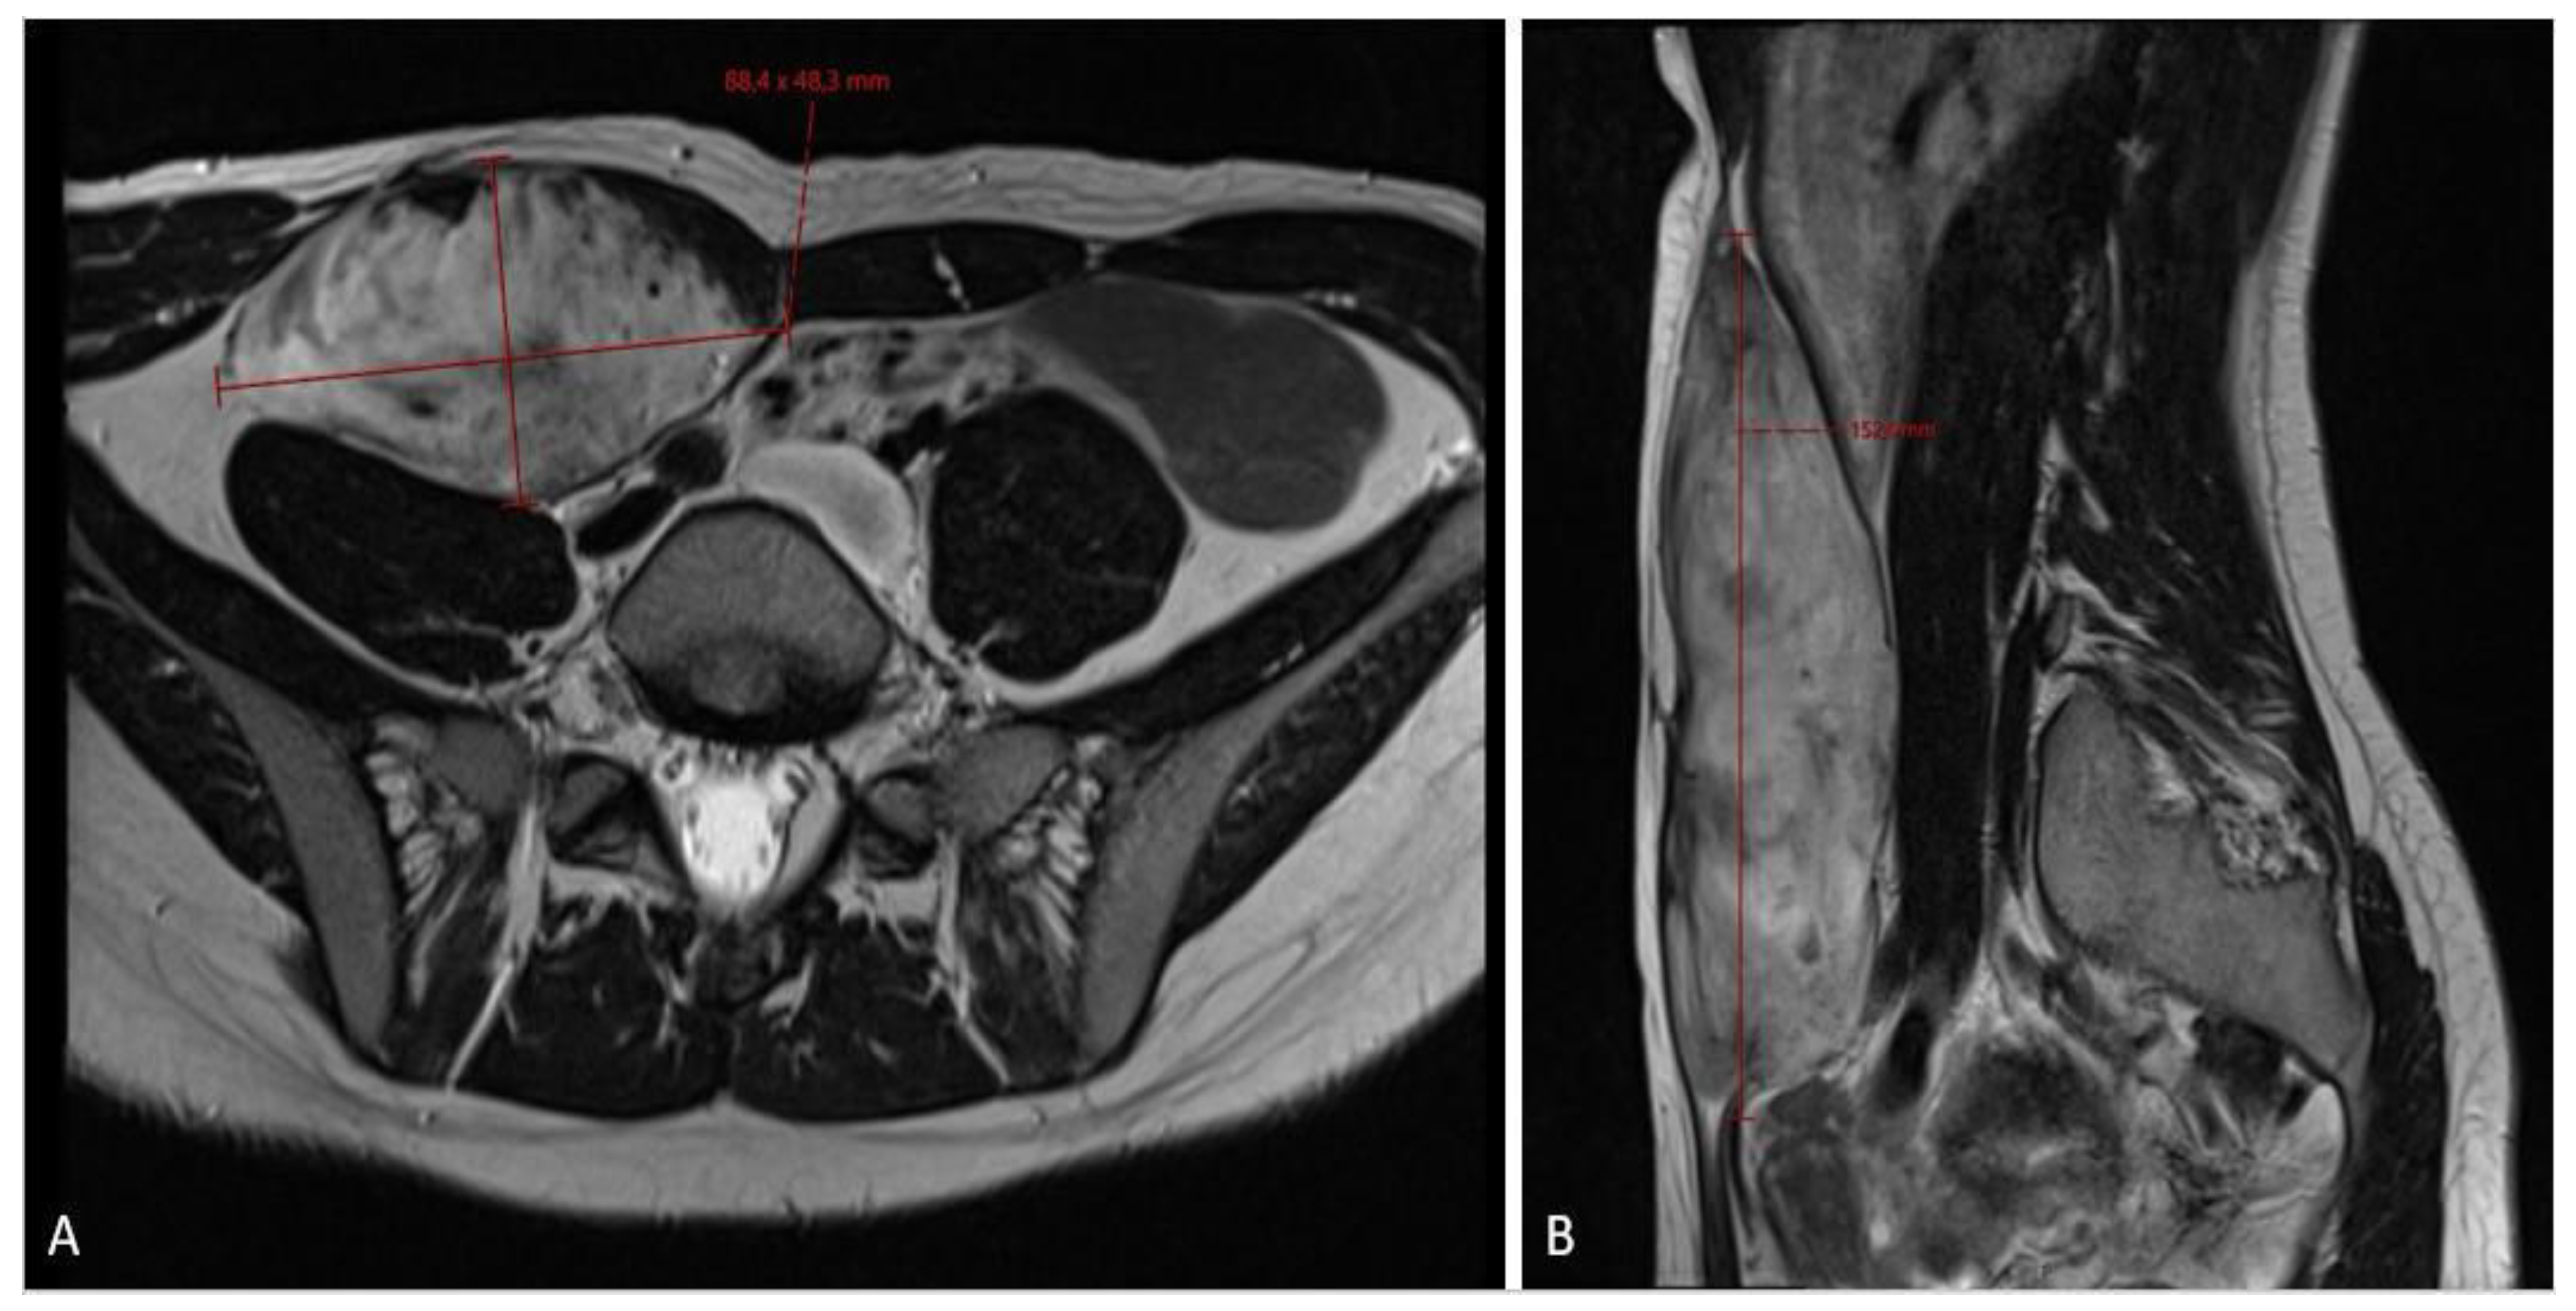

Figure 2.

MRI scan ((A)—axial plane; (B)—sagittal plane) assessment of fibromatosis lesion at the first diagnostic scan, sized 8.8 × 4.8 × 15.3 cm.

When the patient turned 26 (6 years after the surgery), she developed a desmoid tumor sized 12.0 × 4.6 × 6.6 cm on abdominal ultrasound scan (Figure 1) and 8.8 × 4.8 × 15.3 cm on MRI scan (Figure 2) in the anterior abdominal wall on the right side close to the previous trocar point of incision after laparoscopic surgery for FAP and transient-relieving stomy. This was primarily suspected to be sarcoma or a desmoid tumor. A core-needle biopsy was performed confirming the diagnosis of desmoid fibromatous tumor (Figure 3). The tumor board considered the situation as stable, with the possibility for partial spontaneous regression. As the risk for recurrence was assessed to be 50%, no surgery was performed, and she was referred for follow-up with new MRI control in about 3 months. During this follow-up period, she became pregnant and underwent a provoked medical legal abortion in week 6.